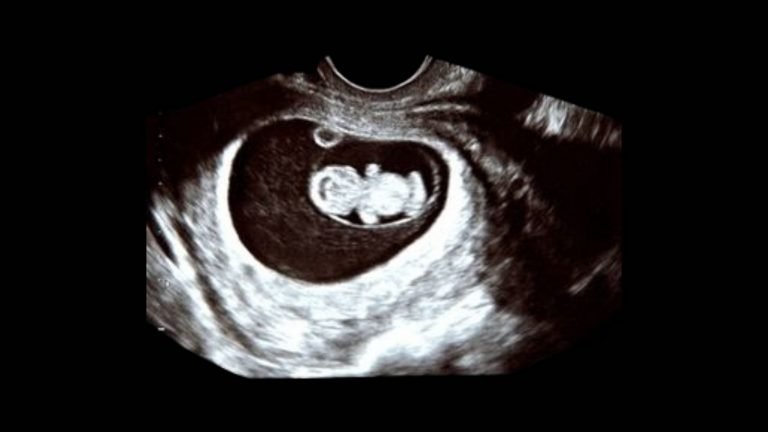

Fetus in the early pregnancy on an ultrasound scan.

An early pregnancy scan, also known as a dating scan or pregnancy confirmation scan, is usually the first ultrasound recommended during pregnancy.

This scan plays a crucial role in confirming pregnancy, assessing the fetal position (whether the pregnancy is inside or outside the uterus), and estimating the expected due date.